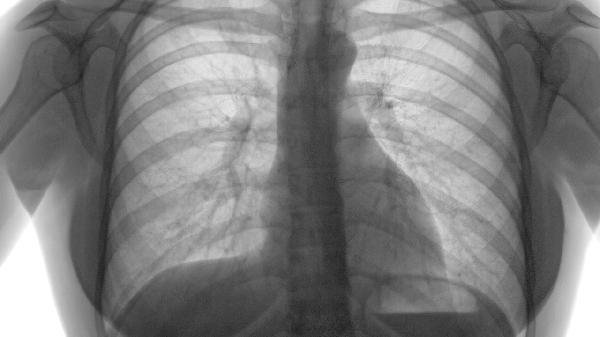

当肺气肿合并肺结核、流感病毒或肺炎链球菌感染时,痰液中可能携带相应病原体。结核杆菌可通过飞沫核传播,需进行痰涂片抗酸染色检测确认。急性感染期痰液变黄绿色或带血丝时需警惕传染可能。